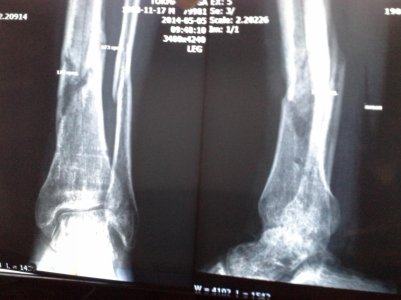

Сегодня сделали снимок, он прилагается.

Описание снимка: Кости нижней конечности порозны. Определяется угловая деформация нижней трети диафиза обеих берцовых костей как результат имевшего место перелома костей. В местах перелома имеются периостальные наслоения. Заключение: Консолидированные переломы костей левой голени в положении углового смещения отломков.

Состояние сына значительно улучшилось! Волнует вопрос, - когда можно будет ходить без гипса. Врач, конечно скажет что-то... но опыта у нее еще мало. Что Вы можете сказать по снимку? Ответьте пожалуйста.

описание консолидированный или консолидирующийся перелом?по снимку очень плохо видно,но гипс снимать еще рано,необходимо видеть конечность очно.

но там сказано, что кости ПОРОЗНЫ... это означает, что еще они хрупкие?

костная мозоль в любом случае изначально будет порозна,нужно время для окостенения,но это не означает,что до этого времени вам нужно ходить в гипсе